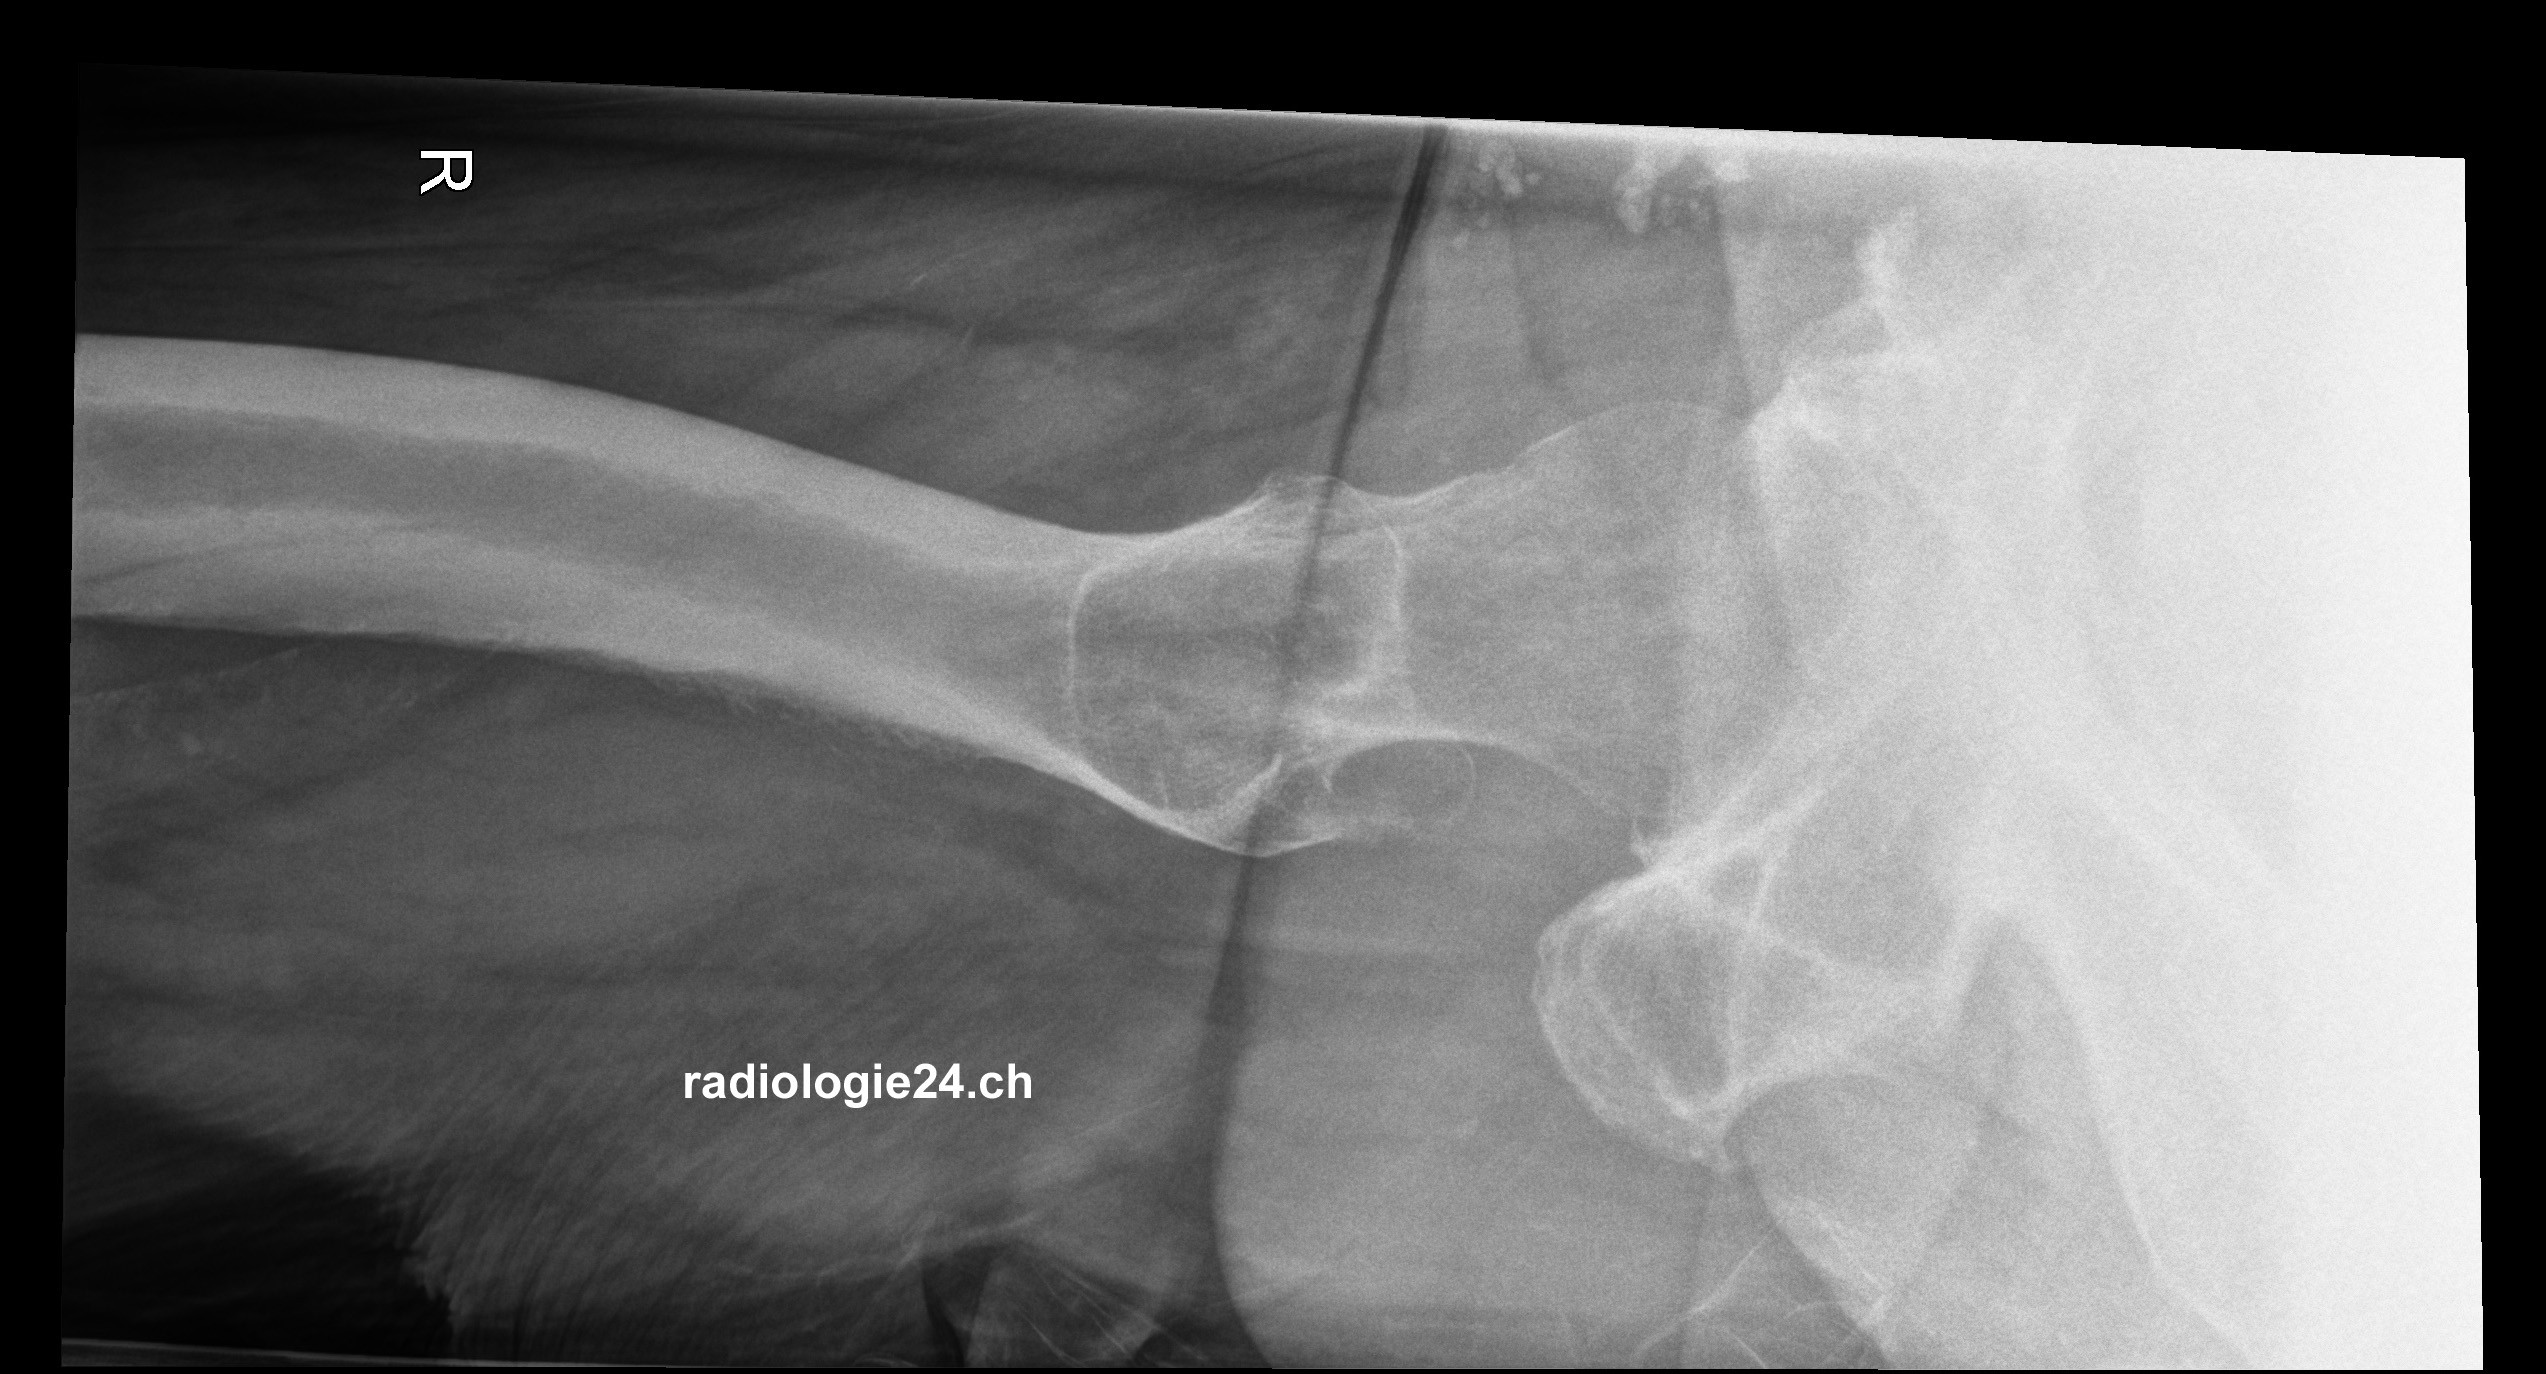

Link zur Auflösung mit ausführlichem Befund:

https://www.radiologie24.ch/radiologie-mediathek/roentgenfall_des_monats